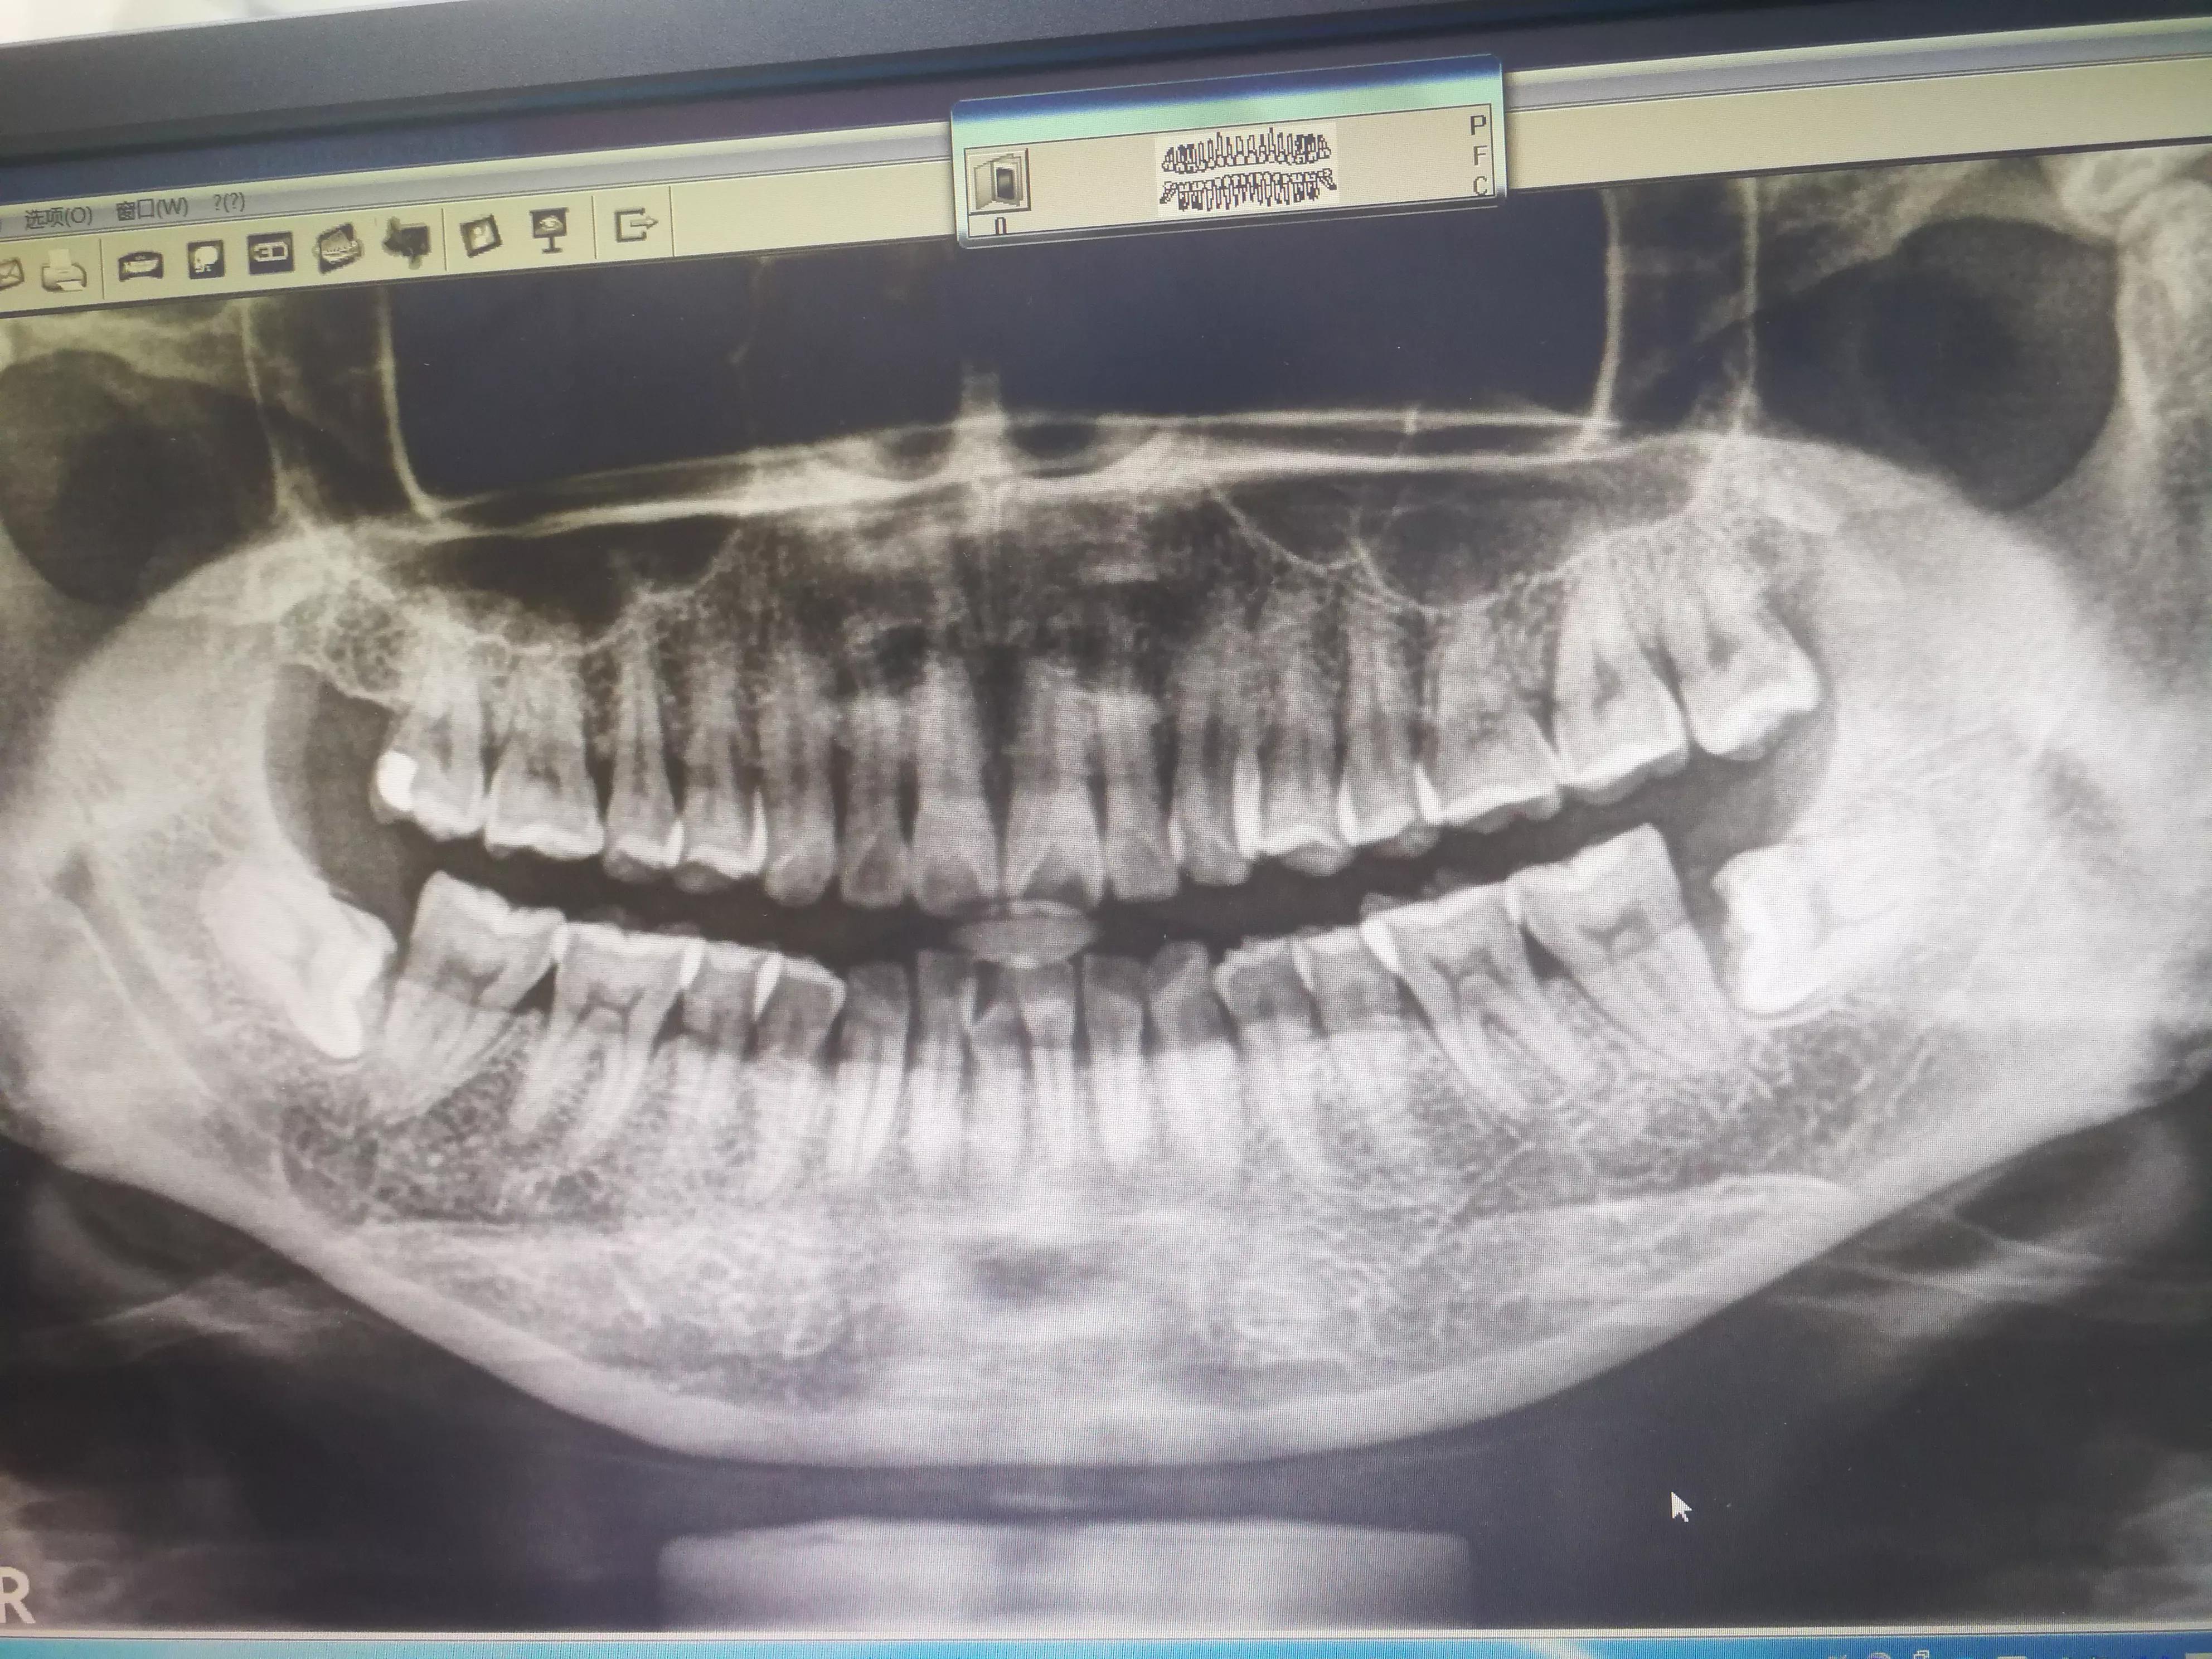

#打卡美好生活#昨天终于下决心拔了左侧上下两颗智齿,因为离家不远是附近医院新开业单独的牙科诊所,和孩子她爹手拉手散步就去了,结果医生说要先拍片还要洗牙,拍了片子是把脑阔搁在一个架子上咬着一个杆杆(感觉古代秋后问斩的那玩意儿),拍完护士要我用自己的手机对着电脑拍一张图片就是下面这张图,

才发现原来右边还深埋了一颗和左边一模一样的姿势躺着,我确定只拔左边上下两颗,洗牙在三楼,一上楼就看见非常童趣卡通的黄色长颈鹿座椅,原来是两个儿童看牙科室,成人在最里面有人在洗,护士说能不能下午再来,也行中午回去好好地大吃一顿,美美地睡了一个午觉才去,先滋滋地洗了牙,然后下楼去拔牙医生那里,已经有人在拔牙了,医生正拿着器械在患者嘴里拉扯着一根黑绳子,看得我头皮发麻,医生抬头看了我一眼还咕噜了一句“这么快就洗完了”,叫我再等一下,于是我就拉着孩子她爹又跑到三楼按着给他也洗了牙,没想到他洗了我两倍的时间,边洗医生小姑凉还边一直说有两颗大牙要拔掉了,等他洗好了下去,那个先来的已经拔好了,用手拖着一坨毛巾包着的按在脸上坐在椅子上,可能是冰袋,头皮又麻了,不是打麻药吗?拔完就这样要冰敷?接着我躺下先补了几颗牙,扑鼻而来的一股胶水味道,脑阔里马上出现粉刷匠打磨墙喷刷油漆的场景,耳边是医生自卖自夸地说现在补牙材料比以前高级多了,我现在用的这个很好,还有更好的但价格太贵,一般人用不起滴,补完牙医生就打了麻药(有点涨不是很疼,医生还表扬我比前面那个患者安静没叫,但是拔上面的牙时又在天花板打了一针麻药疼得我都蹬了好几下腿),先拔的下面的那颗躺着的倒牙,我感觉医生用切、钻、翘、拔、缝等动作捣鼓了快四十分钟才把那颗牙五马分尸地弄出来(还有吸,有个高中生一样的医生被拔牙医生一直吩咐吸我的口水),还缝了针,我还听见孩子她爹在旁边咕了一句“这看不下去了”,我想生女儿剖腹产后都没有背啥止痛棒吃止痛药,这拔两颗歪牙应该忍得住没吃止痛药,万万没想到啊!昨晚麻药消后一直硬挺着,现在左边脸肿得好像含着一个鸡蛋(孩子她爹还说两边都这样胖嘟嘟更好看可爱),今天比昨天疼多了,关键是头也疼,喝水吞口水喉咙都疼,没忍住还是吃了一颗止痛药,现在好些了,右边下颌还有一颗躺着,何时叫醒它有点不敢了,上面的牙是站着的,没有如漫画里弄钩啊锤的,给我拔牙的小伙子骄傲滴说早都不用敲牙齿了,现在有更先进更快捷的高级仪器辅助拔牙,的确分分钟就给拔出来了,除了听得见牙齿脱落牙龈滋滋的声音有点后背发毛以外,感觉像大快朵颐吃鸡腿时撕扯肉到嘴里的声音,接着又是牙齿叮当丢到手术盘里声音,脑海里马上浮现出电影里拔*弹子**出来的场景,医生给揭开蒙在脸上只露嘴巴的绿色布后,我摸着左边没有知觉的脸,活动了一下下巴骨感觉嘴巴张了半天都快合不拢了,起身就看见手术盘里的牙,并没有我想象中有两条腿的样子,一颗已经分尸几块,一颗是条脑袋黑了的“美人鱼”,医生还用他的一次性手套替我装起了这还粘着血的一颗半牙,说可以带回去,现在放在药瓶盖子里就是它们了,